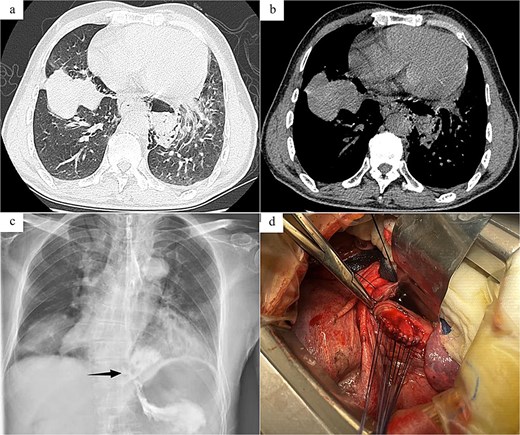

Case 1: The patient, a 67-year-old male, was admitted to Emergency Department due to “hematemesis for 2 h, abdominal and thoracic pain for 1 h.” On admission, imaging studies including chest and abdomen computed tomography (CT) revealed esophageal distal middle-third wall thickening, perihilar pleural edema, pericardial effusion (Fig. 1a and b). Esophagus echoendoscopy showed contrast agent leakage into the perihilar region (Fig. 1c). Electrocardiogram showed no abnormalities. Blood routine test showed that white cell count 11.7 × 109/L, neutrophil count 10.4 × 109/L, neutrophil percentage 89%. In summary, the diagnosis was SRE. In emergent surgery under general anesthesia, laparoscopic repair of esophageal tear was performed. Intraoperative exploration revealed a rupture site located in the lower segment of the esophagus, with a length of about 4.0 cm (Fig. 1d), esophagus and gastric contents (stomach) overflowed at the site of the injury. The surgical steps included removal of foreign bodies, copious irrigation with normal saline until clear, and iodine solution irrigation for disinfection. Subsequently, the surgery trimmed the severely contaminated mucosa and muscular layer of the esophageal perforation until slight oozing of blood, involved interrupted absorbable sutures for full-layer closure of the esophageal perforation, reflushed with iodine solution. Drainage tubes were placed in the mediastinum and chest cavity, respectively. And a gastric tube and a duodenal feeding tube were indwelled. Postoperative care included anti-infection, protective measures, and parenteral nutrition. On the second day after surgery, the patient developed febrile maintained at 38.1°C–38.6°C, and a repeat blood routine examination showed low white blood cell count. The heart rate remained around 125 beats per minute, the blood pressure fluctuated between 80–90/50–60 mmHg, with palpitations, apathy, and involuntary spasms in the limbs. Infectious shock was considered after multi-disciplinary discussion, and the patient was transferred to the intensive care unit (ICU) for upgraded antibiotics (imipenem, vancomycin) therapy, and was given ventilator-assisted breathing, fluid infusion, blood transfusion, enteral nutrition, and other supportive treatment. After 7 days of treatment in the ICU, the septic shock was corrected and the patient was transferred back to the general ward for treatment. Subsequently, the patient was reexamined with upper gastrointestinal radiography and chest CT, which suggested that there was no leakage or stenosis at anastomosis of the esophagus. After a total of 18 days of fasting, the patient began to resume a diet and was discharged in good health.

Radiology images and emergency surgery photos of spontaneous esophageal rupture (Case 1). (a and b) Chest and abdomen computed tomography revealed mediastinal emphysema around the lower segment of the esophagus. (c) Esophagus echoendoscopy showed contrast agent leakage into the perihilar region (arrow). (d) Emergency surgery revealed a rupture site located in the lower segment of the esophagus, with a length of about 4.0 cm, and involved interrupted absorbable sutures for full-layer closure of the esophageal perforation.